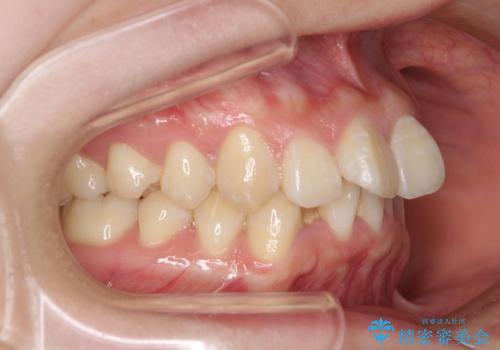

上下前歯の叢生をインビザラインできれいに

- 前歯のデコボコを気にして来院された患者様です。

前歯が重なっていることで口元が閉じにくくなっていたため、歯列全体の側方への拡大と、歯と歯の間を少し削ってスペースを獲得することとしました。

下顎前歯は後戻りを起こしやすいため、舌側を細いワイヤーで固定し、マウスピース型リテーナーで保定を行うこととしました。